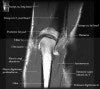

팔꿈치 관절의 MRI 단면 영상

1. Coronal section

1) Collateral ligament

2) Common extensor/flexor tendon group patholgy as well as epicondylitis